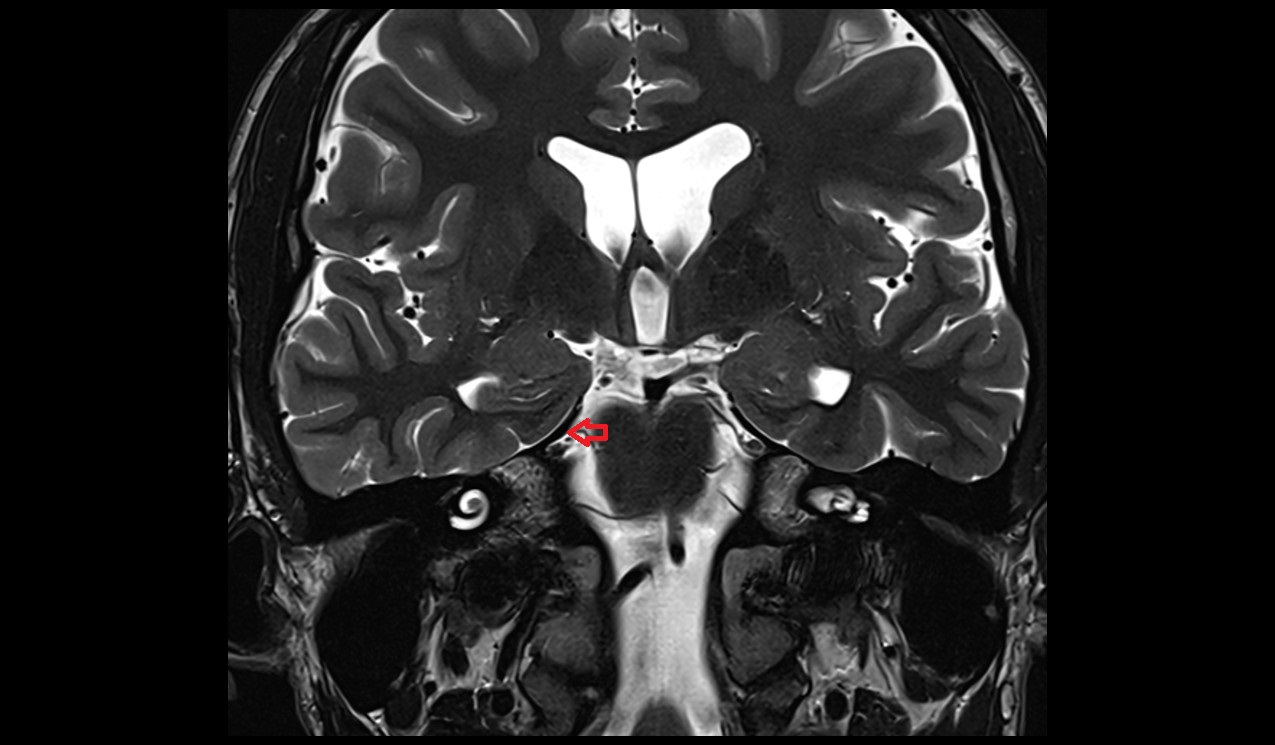

- Hippocampus